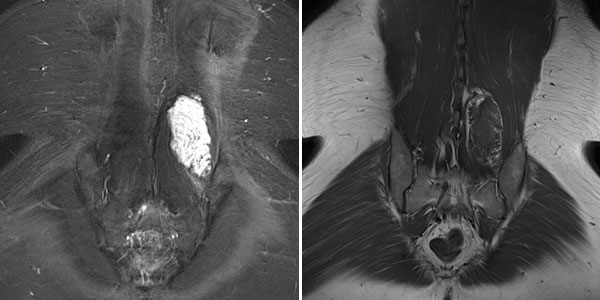

The lesion is very clearly visible in the MRI in coronal plane. In the T2-weighted sequence with fat saturation (left), the lesion is highly hyperintense (white). In the non-enhanced T1-weighted sequence (right), it is virtually isointense to the surrounding back muscle. Note here the fatty tissue visible marginally in the lesion, hyperintense in T1 weighting.

In the axial T2-weighted MRI sequence, the lesion is located in the erector spinae back muscles. Classic fluid-fluid level due to gravity-induced sedimentation effects with the patient lying still in the supine position in the MRI unit.